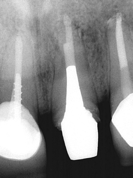

Surgical Endodontic Treatment

Hemisection with Cast Post and Core